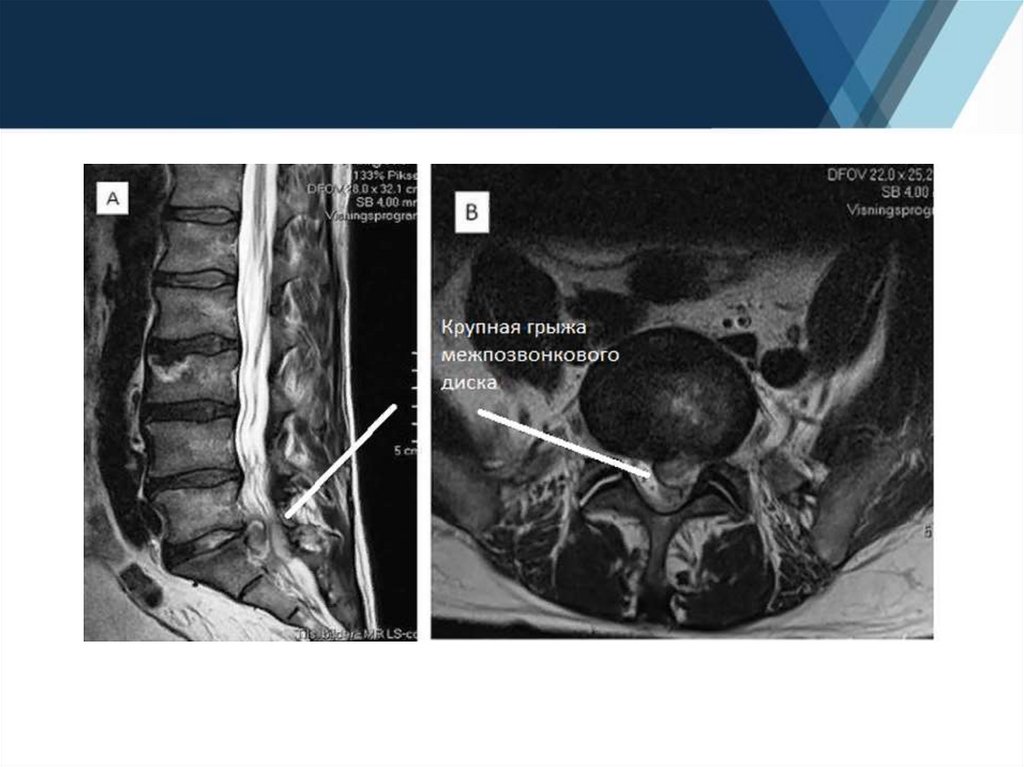

6. Дегенеративно-дистрофические заболевания позвоночника:

- диагностика протрузий и грыж межпозвоночных дисков;

- оценка компрессии спинного мозга, нервных корешков и дурального

мешка;

- оценка стеноза позвоночного канала.